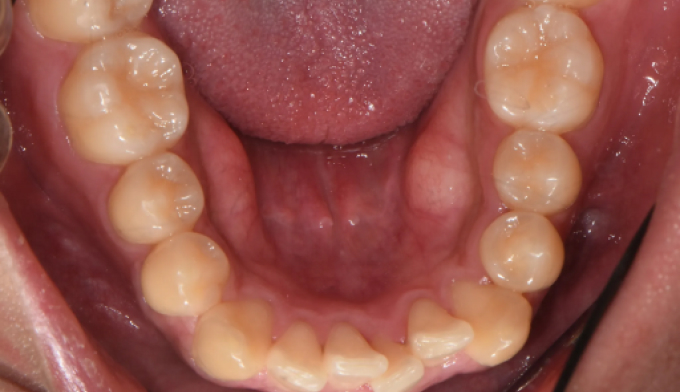

앞니불규칙

앞니를 배열하는데 있어서 필요한 공간이 많지 않은 경우, 전체교정 없이 앞니만 부분적으로 교정하는 방법을 통하여 쉽고 빠르게 치열을 가지런하게 할 수 있습니다. 멀쩡한 앞니를 삭제하고 씌우는 크라운이나 라미네이트 치료를 하지 않아도 됩니다.

교정기간은 7개월 소요되었습니다.